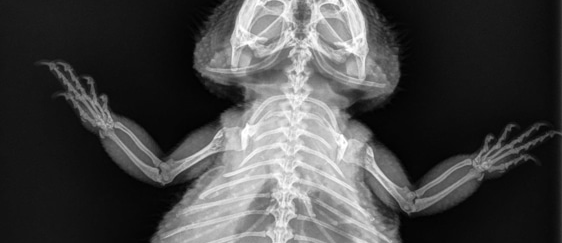

Metabolic bone disease is when an animal experiences weakening of their bones due to causes such as poor nutrition or lack of proper UVB levels, which in turn results in a lack of calcium being absorbed by the body. Without enough calcium to make them strong, the animal’s bones will bend and break just by doing normal everyday functions. Other symptoms of MBD can include swelling of the jaw and limbs, or “rubber jaw syndrome”, muscle tremors, paralysis, and other internal complications, such as nerve damage and organ failure.